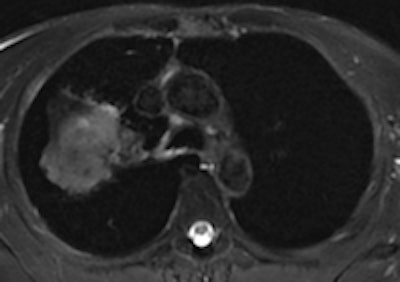

A 50-year old male patient with NSCLC stage pT2b pN2 cM0, imaged with FDG-PET/CT-MR. On coronal PET maximum intensity projection (MIP) image, an FDG-avid tumor in the right upper lobe and a mediastinal lymph node metastasis are seen. All images courtesy of Dr. Martin Huellner.For many years, PET/CT has been the standard modality for staging NSCLC patients. So, before PET/MRI can supplant it for this application, some basic clinical questions need to be addressed, said lead author Dr. Martin Huellner from University Hospital Zurich.